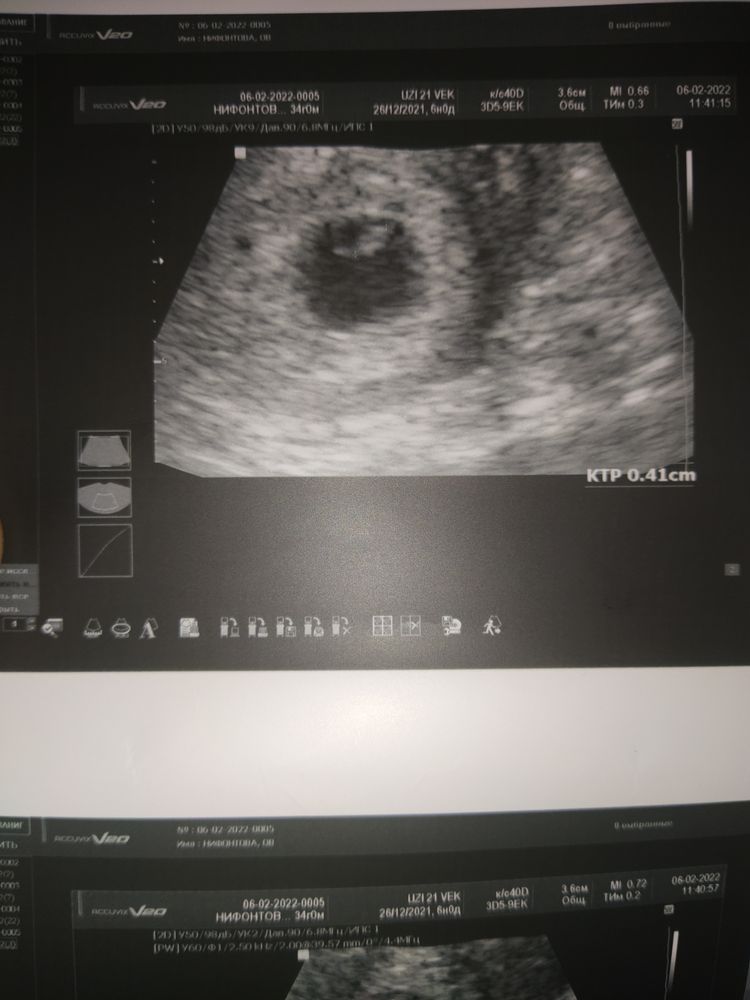

Первле УЗИ 6+0😍

Кристина Калинько, почему?) В прошлый раз очень стремительно рос ХГЧ и на 6+2 было уже с опережением и ктр и сердцебиение